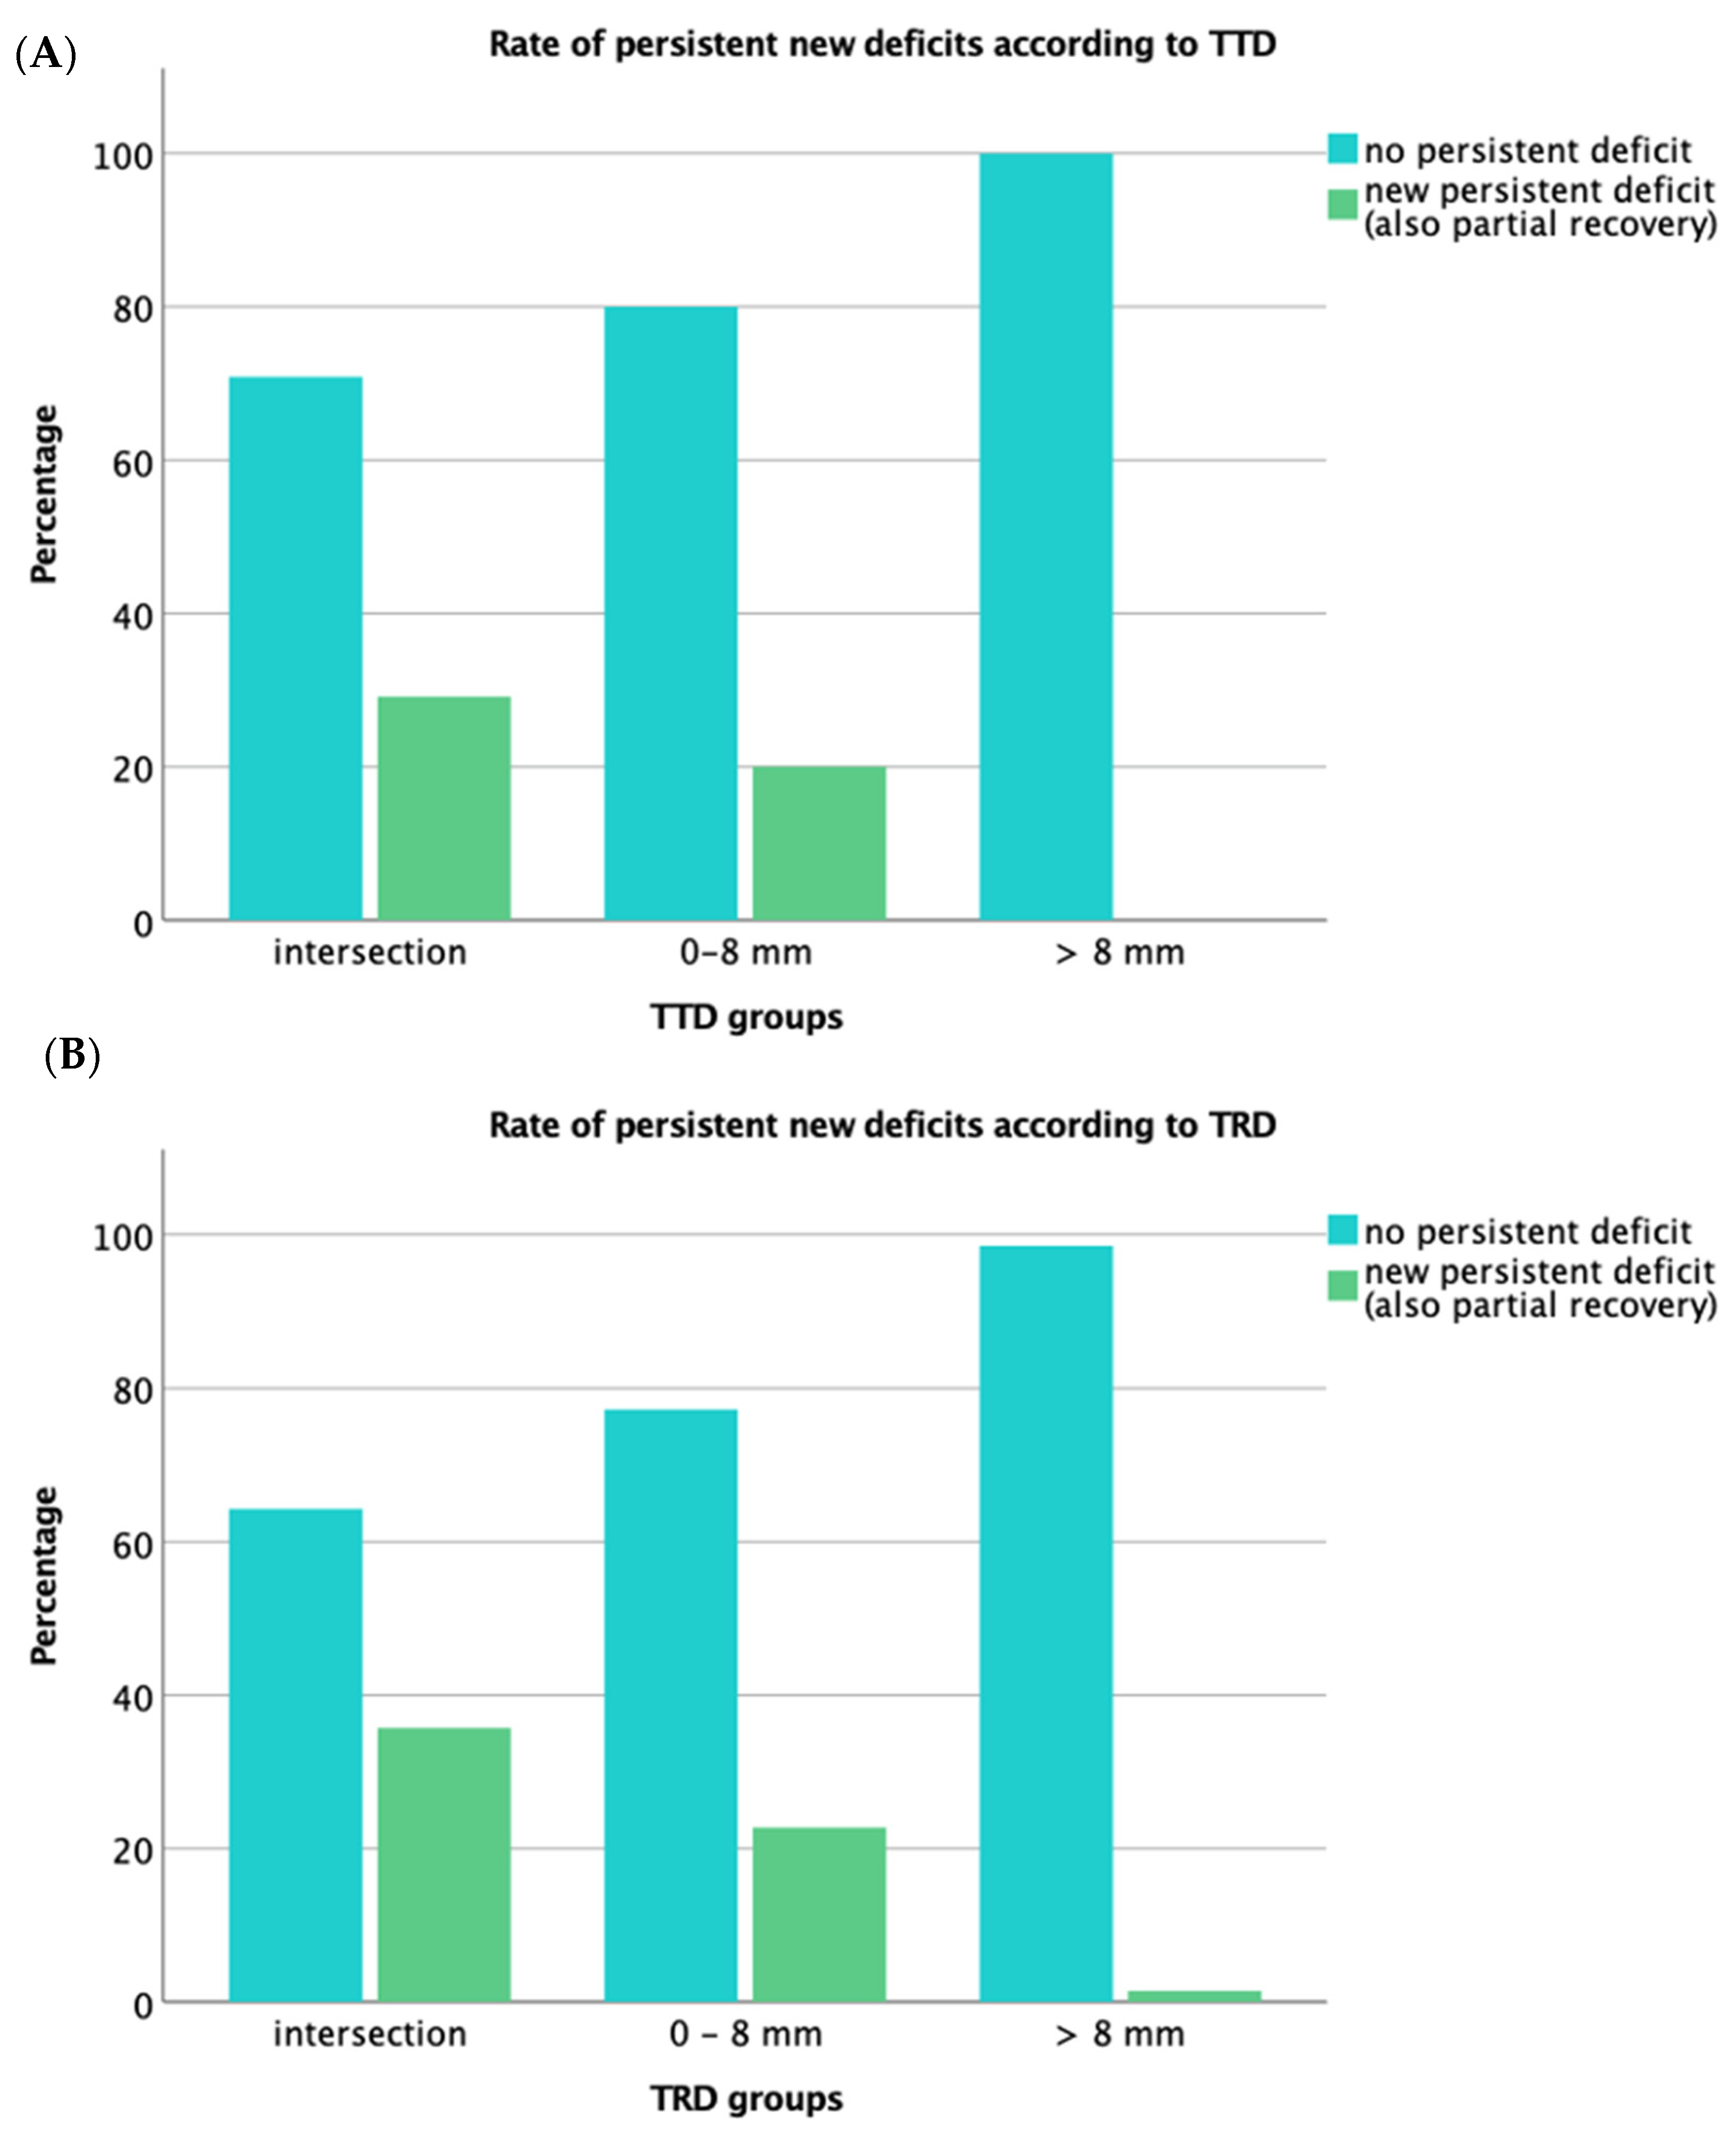

3.4. Functional Outcome

| CST Infiltration | n | Persistent New Deficit (n=): Infiltration (%) | p-Value | Kendall’s Tau-b |

|---|---|---|---|---|

| TTD | ||||

| intersection | 48 | 14 (29.2%) | <0.001 | 0.30 |

| 0–8 mm | 60 | 12 (20.0%) | ||

| >8 mm | 56 | 0 (0%) | ||

| TRD | ||||

| intersection | 28 | 10 (35.7%) | <0.001 | 0.35 |

| 0–8 mm | 66 | 15 (22.7%) | ||

| >8 mm | 70 | 1 (1.4%) * |